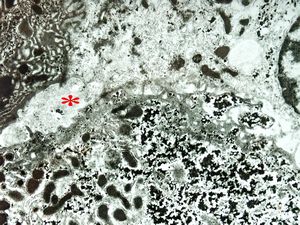

F,7m. | giant cell hepatitis* - dilated primary bile duct

F,7m. | giant cell hepatitis* - dilated bile duct